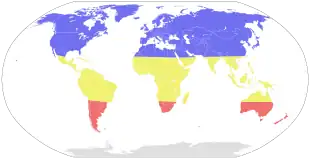

Influenza spreads around the world in yearly outbreaks, resulting in about three to five million cases of severe illness and about 290,000 to 650,000 deaths.[1][4] About 20% of unvaccinated children and 10% of unvaccinated adults are infected each year.[14] In the northern and southern parts of the world, outbreaks occur mainly in the winter, while around the equator, outbreaks may occur at any time of the year.[1] Death occurs mostly in high risk groups—the young, the old, and those with other health problems.[1] Larger outbreaks known as pandemics are less frequent.[2] In the 20th century, three influenza pandemics occurred: Spanish influenza in 1918 (17–100 million deaths), Asian influenza in 1957 (two million deaths), and Hong Kong influenza in 1968 (one million deaths).[15][16][17] The World Health Organization declared an outbreak of a new type of influenza A/H1N1 to be a pandemic in June 2009.[18] Influenza may also affect other animals, including pigs, horses, and birds.[19]

Seasonal variations

Influenza reaches peak prevalence in winter, and because the Northern and Southern Hemispheres have winter at different times of the year, there are actually two different flu seasons each year. This is why the World Health Organization (assisted by the National Influenza Centers) makes recommendations for two different vaccine formulations every year; one for the Northern, and one for the Southern Hemisphere.[121]

A long-standing puzzle has been why outbreaks of the flu occur seasonally rather than uniformly throughout the year. One possible explanation is that, because people are indoors more often during the winter, they are in close contact more often, and this promotes transmission from person to person. Increased travel due to the Northern Hemisphere winter holiday season may also play a role.[176] Another factor is that cold temperatures lead to drier air, which may dehydrate mucus particles. Dry particles are lighter and can thus remain airborne for a longer period. The virus also survives longer on surfaces at colder temperatures and aerosol transmission of the virus is highest in cold environments (less than 5 °C) with low relative humidity.[177] The lower air humidity in winter seems to be the main cause of seasonal influenza transmission in temperate regions.[178][179]

However, seasonal changes in infection rates also occur in tropical regions, and in some countries these peaks of infection are seen mainly during the rainy season.[180] Seasonal changes in contact rates from school terms, which are a major factor in other childhood diseases such as measles and pertussis, may also play a role in the flu. A combination of these small seasonal effects may be amplified by dynamical resonance with the endogenous disease cycles.[181] H5N1 exhibits seasonality in both humans and birds.[182][183]